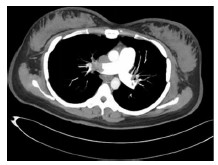

患者女性,30岁,剖宫产术后次日晨起活动后突发喘憋,胸背痛,面色苍白、大汗,伴心率增快,血压下降,意识逐渐转为恍惚。查体:呼吸急促,双肺呼吸音粗、未闻及干湿性啰音,心音有力,律齐,腹部伤口无渗血渗液。立即给予面罩吸氧,建立静脉通道,急查D-二聚体>10 000 μg/L。因高度可疑肺栓塞,立即转入ICU抢救,予锁骨下深静脉置管监测中心静脉压,桡动脉置管PICCO监测心功能,持续面罩吸氧,克赛6 000 U皮下注射抗凝治疗,去甲肾上腺素0.3 μg/(kg·h)联合多巴胺5 μg/(kg·h)维持血压。患者病情进展转为昏迷,立即给予气管插管机械通气,急行胸部增强CT检查回报双肺动脉主干及分支血栓栓塞(图 1)。急查超声心动示:EF45%,右心增大,左心功能减低,二尖瓣返流(中-重度),下腔静脉增宽。经评估风险,立即进行“经静脉导管碎解及抽栓、溶栓术”,术后继续泵入尿激酶60万单位/24 h,严密监测出凝血时间。治疗过程中患者出现少尿、血钾升高、代谢性酸中毒,谷丙及谷草转氨酶均超过1 000 U/L,给予床旁持续血液滤过、保肝降酶治疗。予冰盐水洗胃,耐信抑酸保护胃黏膜、卡洛磺钠治疗胃出血。溶栓24 h后复查肺动脉造影,右肺及左肺动脉主干部分显影,肺动脉压降低,继续尿激酶20万单位/24 h抗凝治疗。细胞病理回报:肺动脉血、外周血及中心静脉血均可见少许角化物(图 2)。给予氢化可的松抗过敏,茶碱、罂粟碱解除气道及血管痉挛,甘露醇降颅压、泰能抗感染治疗。经积极治疗72 h,患者意识转清,生命体征趋于平稳,复查超声心动提示心脏结构及功能正常,予逐步脱机拔管,因少尿继续血液净化治疗,治疗后30 d,患者进入多尿期,肝肾功能等实验室指标逐渐恢复正常,好转出院。

| 图 1 双肺动脉主干栓塞 |